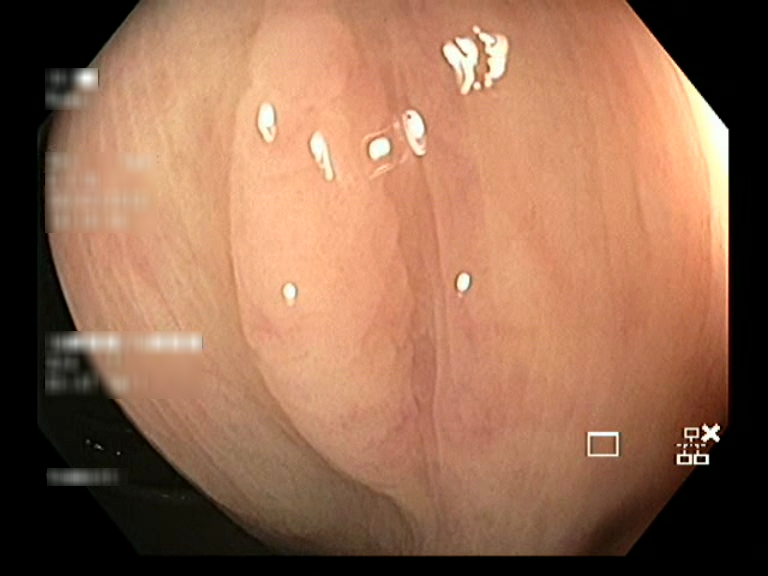

| Lesion | White Light Frame | NBI Frame | White Light Video | NBI Video | Camera Calibration |

| hyperplasic_01 |  |

|

WL.mp4 | NBI.mp4 | cam.xml |